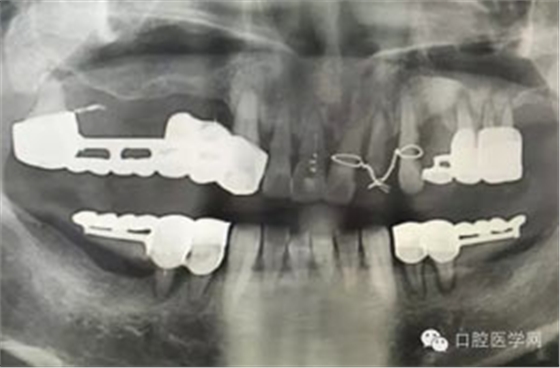

做根管的,都想做些難度大一點(diǎn)的,彎曲根管了、斷針了,可是臨床上很多時(shí)候是中等及以下難度的居多,我們要做的是盡我們所能做好這一部分,將我們力所能及的做好,而不是不切實(shí)際的幻想做一些我們條件設(shè)備不夠的病例。有些時(shí)候看到一些病例,很難想象是我們同行做的,我們是人,而不是神,我們也需要生活,我們追求效益沒有錯(cuò),我們給患者推薦好的材料,最終受益多的還是患者,這沒有錯(cuò),但是我們不是賣產(chǎn)品的,我們的本質(zhì)是醫(yī)療,不是流水線上的工人,將商品加工賣出去,我們所做的一切都是建立在符合修復(fù)設(shè)計(jì)原則的基礎(chǔ)上的,如若不符合,我們做的再美觀,再便宜,那又有什么意義呢?無論我們做什么樣子的修復(fù)體或者是治療,我們的標(biāo)準(zhǔn)是一致的,教科書上有明確的規(guī)定,我們這社會(huì)也有畸形,就拿簡(jiǎn)單的冠修復(fù)來說,我們花費(fèi)的精力是差不多的,我們需要的步驟是一樣的,但是價(jià)格差別那么大,是我們自己制定價(jià)格的問題,還是社會(huì)的問題?如若我們的冠的價(jià)格的制定差別不大,我們將更多的心思放到醫(yī)療本身上面,那么最終受益的還是患者,可是現(xiàn)在是顛倒的,我們成了產(chǎn)品的推銷者,整天想著怎么樣將價(jià)格高的冠賣給患者,而忽略了提高學(xué)習(xí)我們自身專業(yè)能力,我們整天想著怎么樣將環(huán)境打造的多么的好,然而材料上面卻是怎么樣的省怎么來,什么便宜用什么,裝修上面我們可以花很多,材料我們卻很摳,有時(shí)候我們材料買很好,可是我們卻束之高閣,很多時(shí)候我們講理念,講概念,可是我們卻很少腳踏實(shí)地的去做我們的專業(yè),只是用這些新鮮的名詞去和患者溝通。給大家看幾張不良的修復(fù)設(shè)計(jì)。

病例1:患者迫切希望保留自己的這一顆牙齒,根尖周陰影比較大,二度松動(dòng).而且旁邊有種植修復(fù)體,和患者溝通好后,治療好后觀察一個(gè)月后冠修復(fù),因?yàn)橛蟹N植的后期修復(fù),所以有了機(jī)會(huì)觀察,術(shù)后三個(gè)月和術(shù)后四個(gè)月,根尖恢復(fù)的還算不錯(cuò),希望能夠繼續(xù)觀察下去.這樣子的病例,做的時(shí)候我們一定要非常的小心,和患者要有充分的溝通以及不同科室的溝通然后決定怎么樣做比較好,假如就是出現(xiàn)了問題,到時(shí)候我們也比較好處理些,免得我們自己到時(shí)候不好收?qǐng)觥?/span> 病例2:364647中齲的樹脂充填,現(xiàn)在樹脂的充填材料非常之多,有些時(shí)候,我們感覺有了好的材料我們就可以做出好的修復(fù),可是這是在我們有扎實(shí)的基本功的基礎(chǔ)上的,我們可以沒有那么好的樹脂,那么多的顏色選擇,修復(fù)的那么的逼真,但是我們至少要恢復(fù)患者牙齒的功能,將腐質(zhì)去除干凈,薄壁弱尖消除掉,選擇好適應(yīng)癥,給患者以盡可能好的修復(fù)。 來源于KQ88